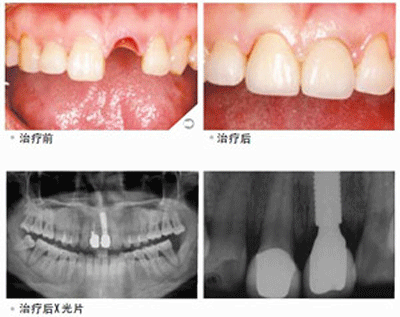

种植门牙案例分享:家住江北区的张先生因为不小心导致门牙摔掉了一颗,门牙缺失后的张先生马上打车来到了福州爱尚贝臣口腔门诊部有限公司。到院后种植牙医师为其做了口腔健康检查,并根据张先生的个人情况为其推荐了欧洲顶级种植体。经过一个小时的手术后,张先生的门牙又从新长了出来。